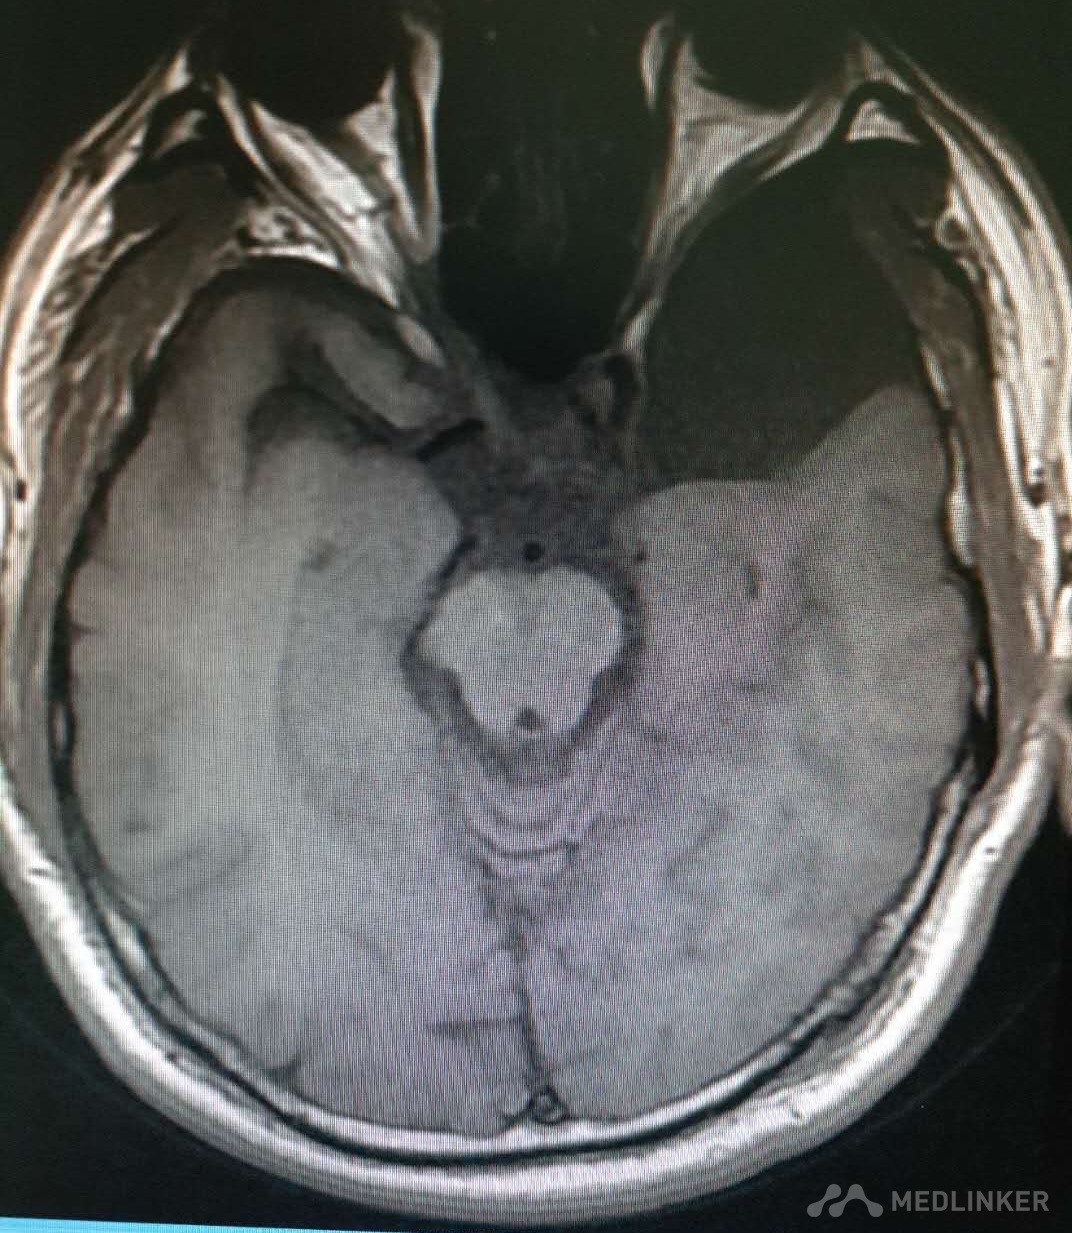

慢性硬膜下血肿

初步诊断:慢性创伤性硬膜下血肿  蛛网膜囊肿 确定诊断:慢性创伤性硬膜下血肿  蛛网膜囊肿 入院以来,完善各方面检查,予以甘露醇脱水治疗,营养神经,抗感染,止血及补充电解质等对症支持治疗。